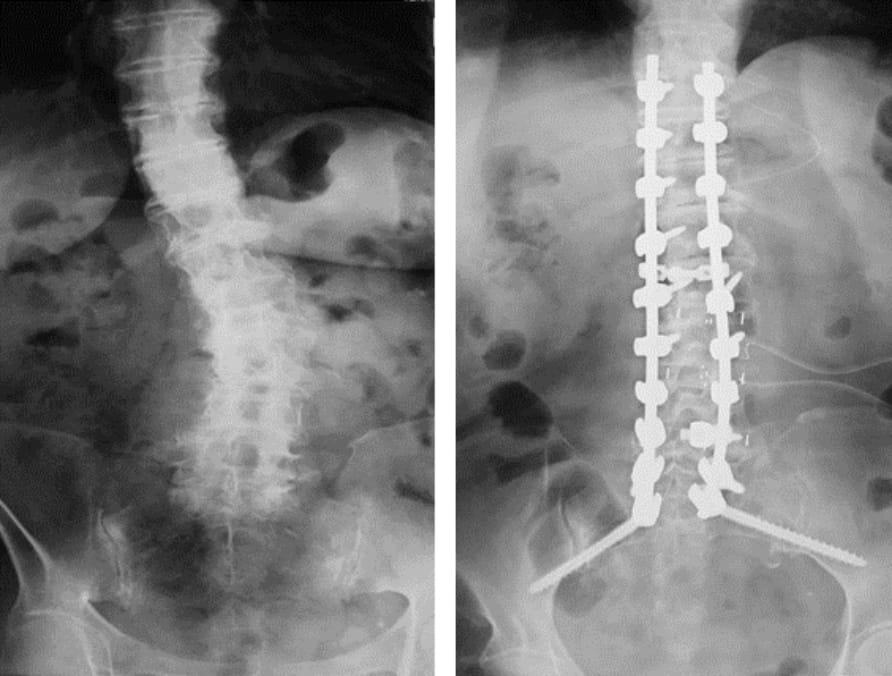

脊椎変形矯正(きょうせい)手術

曲がった背ぼねを真っすぐに矯正する手術です。体の負担はやや大きくなりますが、姿勢が矯正されバランスのよい背ぼねが維持されます。思春期側弯症に対する外来診療や装具治療も行っています。また最近は高齢化に伴い、背ぼねが曲がって猫背(ねこぜ)のようになったり、横に曲がってしまったりする人(側弯症)が多く受診されます。

適応がある場合は、インプラントによる矯正手術によって、姿勢を直すことが可能です。体のバランス不良、姿勢維持の困難な人、慢性の腰痛のある人に適応されます。